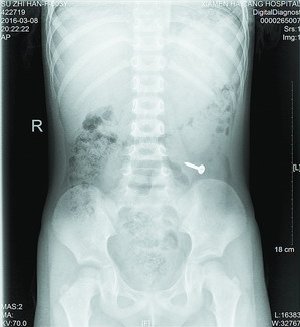

当天值班的叶医生了解情况后,马上安排小桐做X光片检查,检查影像一出来,大家都吓了一跳,只见小桐左下腹清晰地躺着一个金属异物。经与小桐再三辨认,确定是一颗螺丝钉。外科徐医生接诊后表示,患者年龄太小,手术损伤大,且目前没有腹痛、腹膜炎等肠穿孔征象,螺丝钉不是很大,有可能自行排出,便建议随访,让患儿多吃些富含纤维素的食物,如韭菜、芹菜,以促进消化道蠕动,加速螺丝钉的排出。同时,医生告知小桐父母需密切观察大便中是否有钉子排出,如有呕血、腹痛、发烧等异常情况,需马上就医。3天后,小桐再来海沧医院拍片复查,发现螺丝钉已经顺利排出了,虚惊一场。